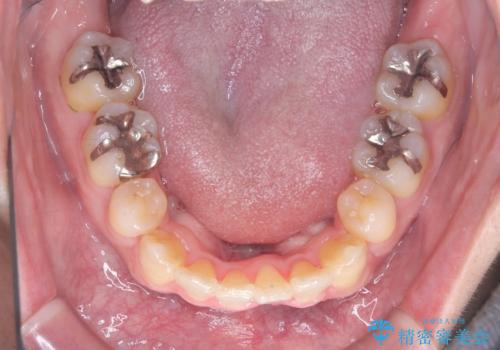

- 「歯のデコボコと前歯が引っ込んでいるのを治したい」を主訴に来院された患者様です。

デコボコの量が多かったため上下左右4を抜歯してワイヤー矯正で治療を行いました。